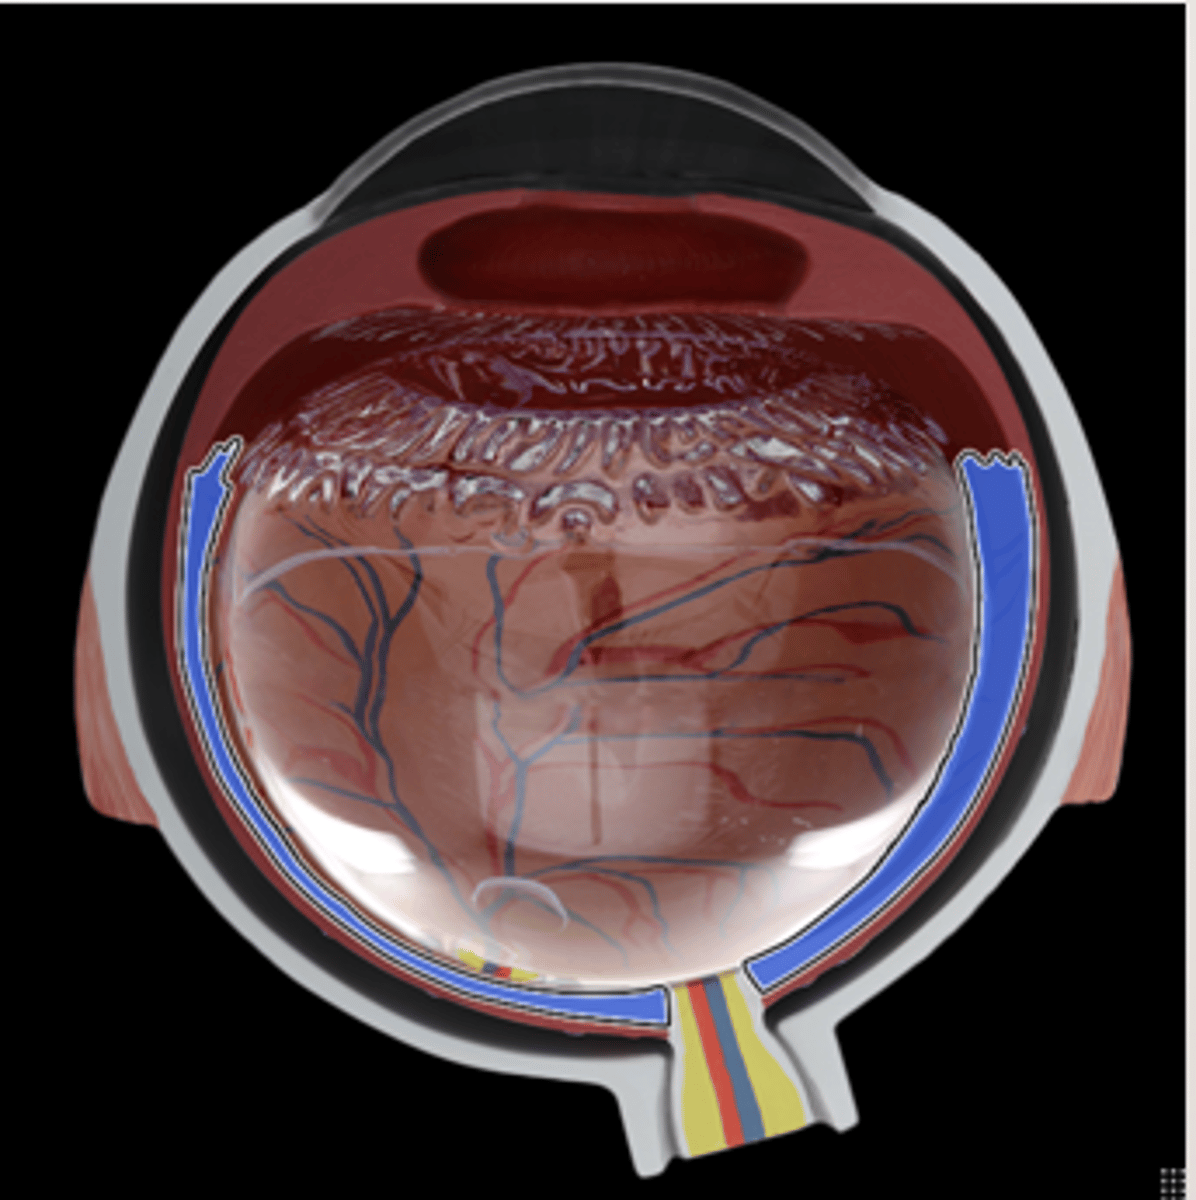

Retina

ciliary body

lens of cow`s eye

cornea

sclera

white of the eye

choroid

Iris

optic nerve

vitreous humor

soft, jelly-like material behind the lens in the viterious chamber, helps maintain shape of eyeball